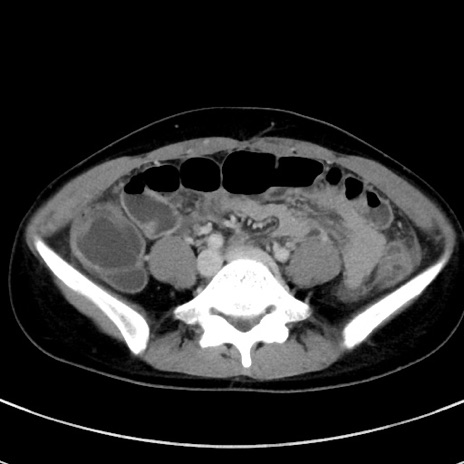

症例17(横断像)

【症例】20歳代女性

【主訴】嘔吐、下腹部痛

【現病歴】昨日夕食後に嘔吐し下腹部痛が出現。本日になっても嘔吐持続し改善しないため来院。

【身体所見】意識清明、BT 37.2℃、BP 108/67mmHg、腹部:平坦、やや硬、下腹部正中から右にかけて圧痛あり、反跳痛軽度あり、tapping pain(+)。

【データ】WBC 13600、CRP 14.94